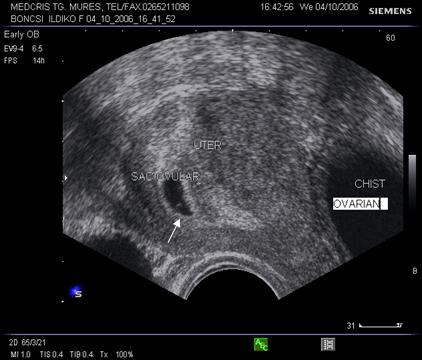

diagnosticul diferential al fibromului uterin si al altor tumori pelvine

Fig. Nr.7. Sac gestational intrauterin ( cu sageata ) la ecografia transvaginala, coroana trofoblastica